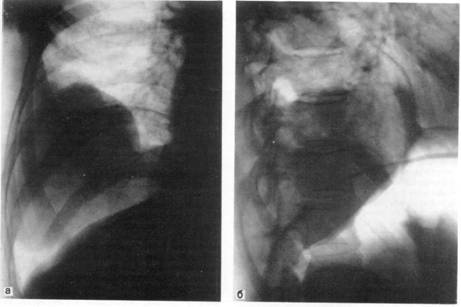

Показанием к введению воздуха или кислорода в брюшную полость с

последующим рентгенологическим обследованием являются образования, прилежащие к

нижним долям легких и куполу диафрагмы, когда не удается ответить на вопрос:

располагаются ли они в легком, исходят из диафрагмы или находятся в поддиафрагмальном

пространстве, например в печени (рис. 4).

Рис. 4. Доброкачественная опухоль

правого легкого в условиях искусственного пневмоперитонеума.

а — прямая рентгенограмма; б — боковая

рентгенограмма.